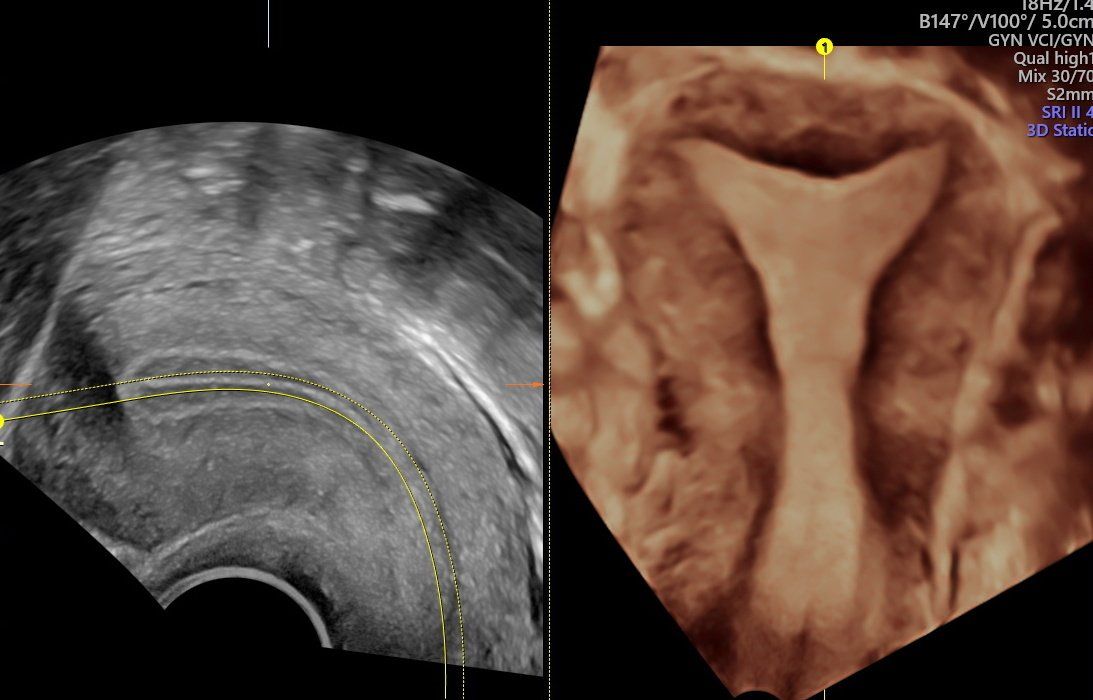

L’ecografia dell’addome risulta un’ indagine molto utile nella valutazione delle patologie del fegato, della colecisti, delle vie biliari, del pancreas, della milza, dei reni, della vescica, della prostata, dell’utero, delle ovaie.

La diagnostica Eco-Color-Doppler si rende utile sia nello studio degli organi interni sia nella valutazione dei distretti vascolari arteriosi e venosi. Gli esami eco-color-Doppler sono indicati per lo studio delle carotidi/tronchi sovra-aortici (patologie cerebro-vascolari e cardiologiche), per la valutazione dell’aorta addominale (aneurismi, dissecazioni), per la valutazione delle arterie degli arti inferiori (arteriopatia ostruttiva, diabete), per la valutazione delle vene degli arti inferiori (insufficienza venosa, varici arti inferiori).